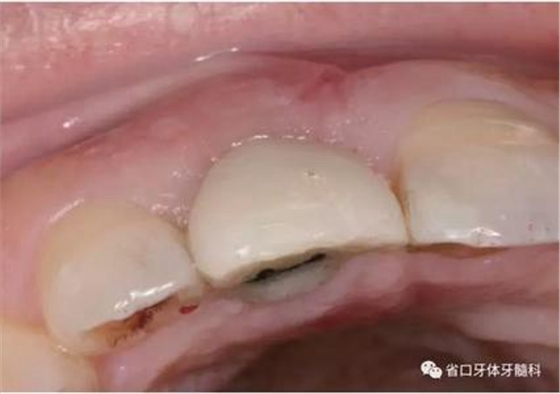

1.?病例簡介 43歲女性患者,主拆:右上前牙松動不適數(shù)日要求修復(fù)。現(xiàn)病史:患者數(shù)年前右上前牙因“齲壞”于外院行根管治療(具體不詳),數(shù)日前牙冠松動不適,現(xiàn)覺影響咀嚼及美觀,遂來我院要求進(jìn)一步診治。否認(rèn)高血壓、心臟病等重大疾病,否認(rèn)結(jié)核、肝炎等傳染病史,否認(rèn)手 術(shù)、輸血史等,未發(fā)現(xiàn)藥物過敏。無吸煙習(xí)慣。臨床檢查:口外觀顏面基 本對稱,皮膚無紅腫破潰,顳下頜關(guān)節(jié)區(qū)無彈響、雜音、壓痛,開口度約 37mm,開口型“↓”,頜下、刻下和頸部未及腫大淋巴結(jié)。中位笑線??趦?nèi)檢查,口腔衛(wèi)生可,色素(+),BOP(-),PD=2mm,上頜右側(cè)中切 牙冠部變色,冠根折斷至齦下3mm,叩不適,松動Ⅱ°~Ⅲ°。牙齦稍紅, 齦緣水平及齦乳頭高度可,屬于中厚齦生物型,附著齦寬度約5mm,唇系帶附著可。上頜右側(cè)中切牙缺牙間隙與對側(cè)同名牙一致,約>7mm,修復(fù)空 間良好。與對頜牙覆合覆蓋正常。MCT檢查示上頜右側(cè)中切牙冠根折斷至骨 下,根管內(nèi)見充填物,根充不全,根尖見陰影,大小約3mm×3mm。牙槽窩根方可用骨量可,唇側(cè)骨壁完整,冠方骨壁厚度約1mm。

圖2 術(shù)前口內(nèi)照

圖3 術(shù)前口內(nèi)照

圖4 術(shù)前X線片